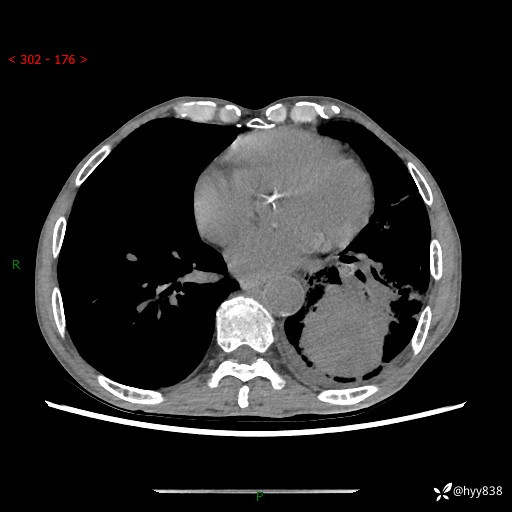

77岁/男,腹痛2月,CT发现左肺占位1天。巨大肿块,肺内或肺外来源…结果公布~

主诉:腹痛2月,CT发现左肺占位1天

现病史:患者于2025年9月间断左下腹胀痛,在当地镇卫生院行彩超检查考虑泌尿系结石,行止痛排石对症治疗未见明显好转;1天前腹痛症状加重,至当地市第三人民医院行CT检查:左肺下叶巨大团块状软组织影,考虑肿瘤性病变,建议增强CT检查;左侧胸腔积液;纵膈内淋巴结肿大;双肺肺气肿;右肺中叶纤维灶。为进一步求治,来我院就诊。

胸部CT平扫+增强